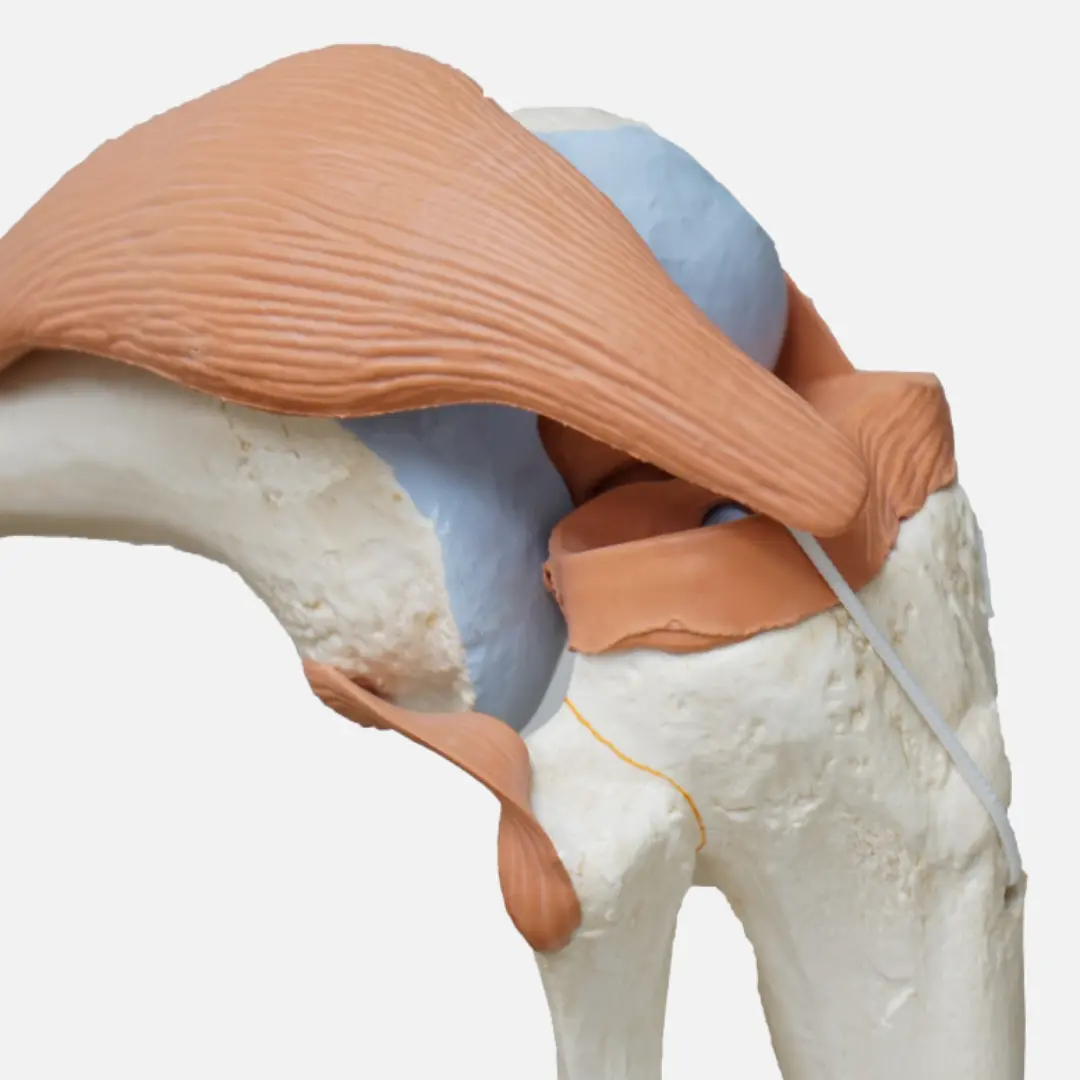

- 글루코사민

- 관절 연골의 주요 구성 성분

- 연골 재생과 관절 통증 완화에 도움